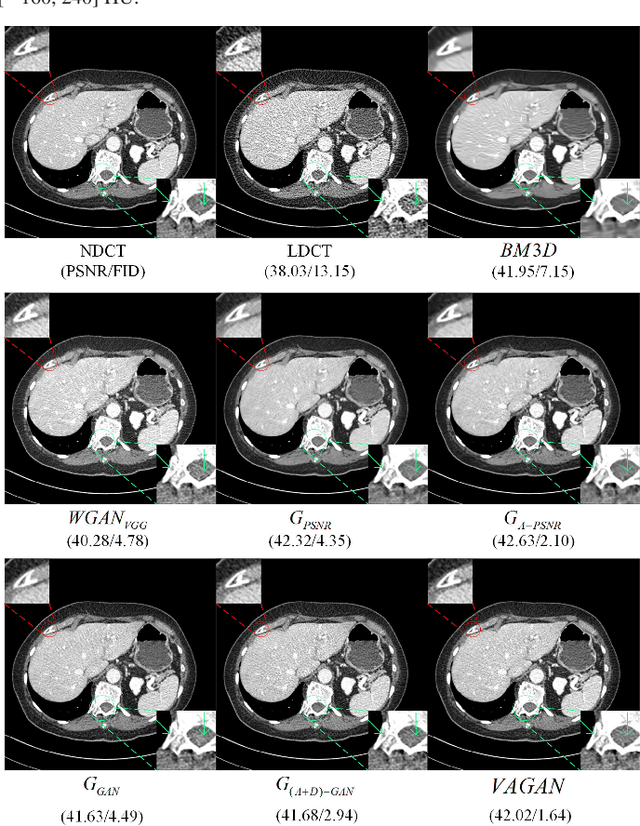

Noise and artifacts are intrinsic to low dose CT (LDCT) data acquisition, and will significantly affect the imaging performance. Perfect noise removal and image restoration is intractable in the context of LDCT due to the statistical and technical uncertainties. In this paper, we apply the generative adversarial network (GAN) framework with a visual attention mechanism to deal with this problem in a data-driven/machine learning fashion. Our main idea is to inject visual attention knowledge into the learning process of GAN to provide a powerful prior of the noise distribution. By doing this, both the generator and discriminator networks are empowered with visual attention information so they will not only pay special attention to noisy regions and surrounding structures but also explicitly assess the local consistency of the recovered regions. Our experiments qualitatively and quantitatively demonstrate the effectiveness of the proposed method with clinic CT images.